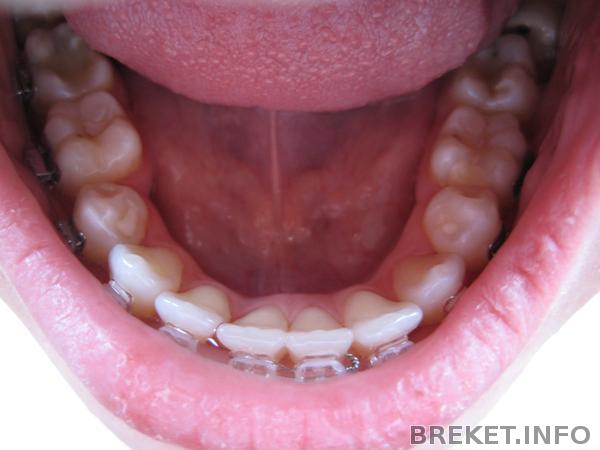

Между 1-ми на НЧ была щель, завязали это дело проволочкой, щель моментально испарилась, но появилась щель между 1-ей и 2-ой((( Буду снова "дырявая ходить" ![]()

Про ретейнеры: на НЧ обязательно надо несъемник и съемный, на ВЧ до конца не поняла. Один надо обязательно, вроде бы несъемник, но я для подстраховки, наверное, закажу оба. Еще про НЧ она сказала, что там, где удаляли зубки, чтобы не разъехалось (а щель появилась с проблемной стороны снова после снятия чейна((((( печальбеда, а не промежуток), тоже как-то закрепит. Вроде бы капнет этим составом. Вобщем гадать не буду, на снятии все будет понятно.

8-ки на НЧ нужно будет удалять, особенно левую! Она еще и с кариесом. Орта сегодня сказала в очередной раз, что она ей очень не нравится. Удалять будем планово, предварительно подготовившись.